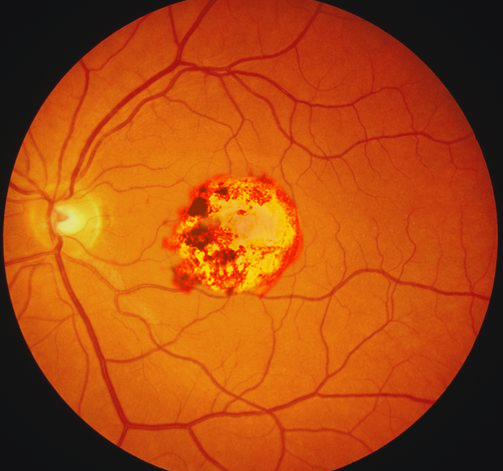

Toxoplasmosis Gondii Chorioretinitis

Toxoplasmic chorioretinitis - Wikipedia A typical chorioretinitis by toxoplasma Ocular Toxoplasmosis: Overview, Pathogenesis, Congenital Versus ... Toxoplasmosis - EyeWiki Fundus photograph of left eye showing active chorioretinitis of ... Toxoplasmosis Gondii Chorioretinitis